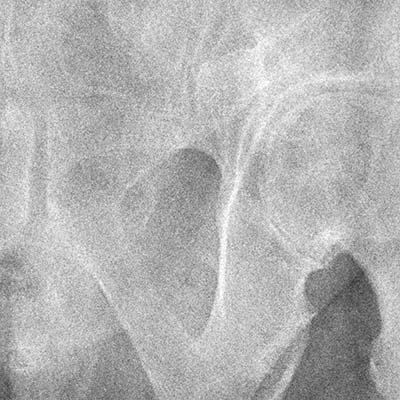

2. Comparaison de la réduction du bruit basée sur le sujet

Aucun traitement

Traitement conventionnel

NR intelligent